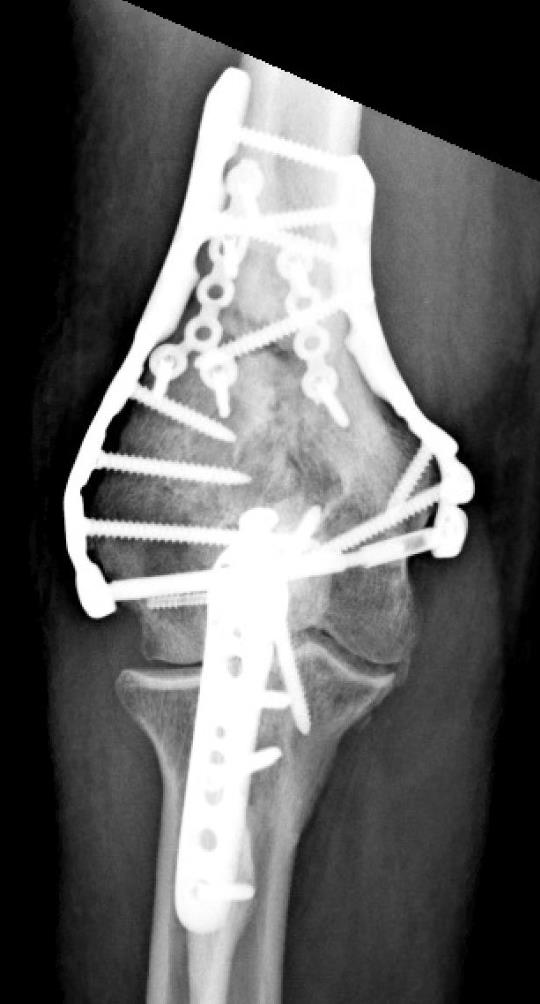

• TiBeam® Assembly

• Use Trochlea Compression Screw Insertion Tool to push out the trochlea K-Wire.

• Place Female Trochlea Compression Screw on the tool tip to protect internal threads.

• With T-10 Driver, insert the female TiBeam® component while pulling the Insertion Tool until fully seated.

• Remove the Insertion Tool and insert the male TiBeam®.

• TiBeam® Compression

• With both drivers in place, engage the male and female components and compress the trochlea fragments.

• Confirm TiBeam® engagement and compression with fluoroscopy.

• Trochlea support screws - medial plate

• Remove the provisional fixation from the Epicondylar Holes and perform final fixation with the chosen Screws.

• Starting with the third hole of the medial plate, work proximally to finish inserting all Metaphyseal Screws

• Repeat for lateral side.

• Diaphyseal function

• Fill the remaining holes in the humeral shaft FreeFix® slots with 3.5mm locking or compression screws using the HPS or 3.5mm Thread-In Drill Guide, and 2.7mm x 50mm Drill Bit.

• When reduction is complete, insert a Locking Cap into each distal node to create a fixed TiBeam® construct.

• Closure

• Once fixation is complete, reduce the olecranon and apply the Proximal Ulna Plate.

• Use the Home-Run Screw to ensure compression across the osteotomy site.

• Fill all the screw holes for optimal fixation.